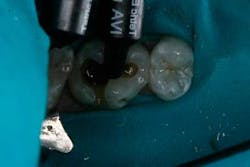

The tooth was prepared and a total etch technique utilizing 37% phosphoric acid was performed (Figs. 3 through 5). After the etchant was rinsed, a desensitizer was placed and blotted to leave a moist dentin surface for bonding (Fig. 6). The bonding agent was applied; the ethanol solvent was air evaporated using a warm air dryer; and the adhesive light-cured for 10 seconds (Figs. 7 and 8).

Fig. 6.

The depth of the cavity was determined to be 4 mm or less. The bulk-filled composite (Tetric EvoCeram® Bulk Fill) was placed in the preparation (Figs. 9 and 10). In this case, the first increment was placed, followed by additional material that was adapted to the tooth anatomy (Figs. 11 through 13). After further refining, the bulk-fill composite was light-cured in one increment for 10 seconds (1,200 mW/cm2).